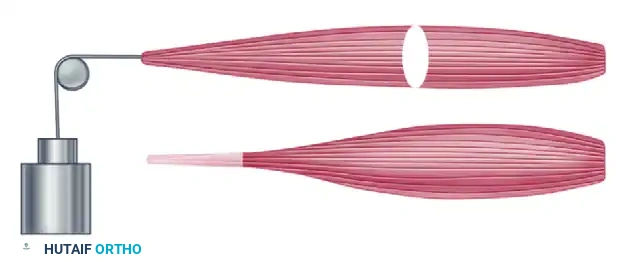

If the ulnar collateral ligament has been detached from the proximal phalanx, it can be reinserted with a direct suture, a suture anchor, or a pull-out wire. While modern micro-suture anchors (1.3 mm to 2.0 mm) are frequently utilized for their biomechanical strength and lack of external hardware, the classic pull-out wire technique remains a highly reliable, time-tested method, particularly when suture anchors are unavailable or if the bone quality is poor.